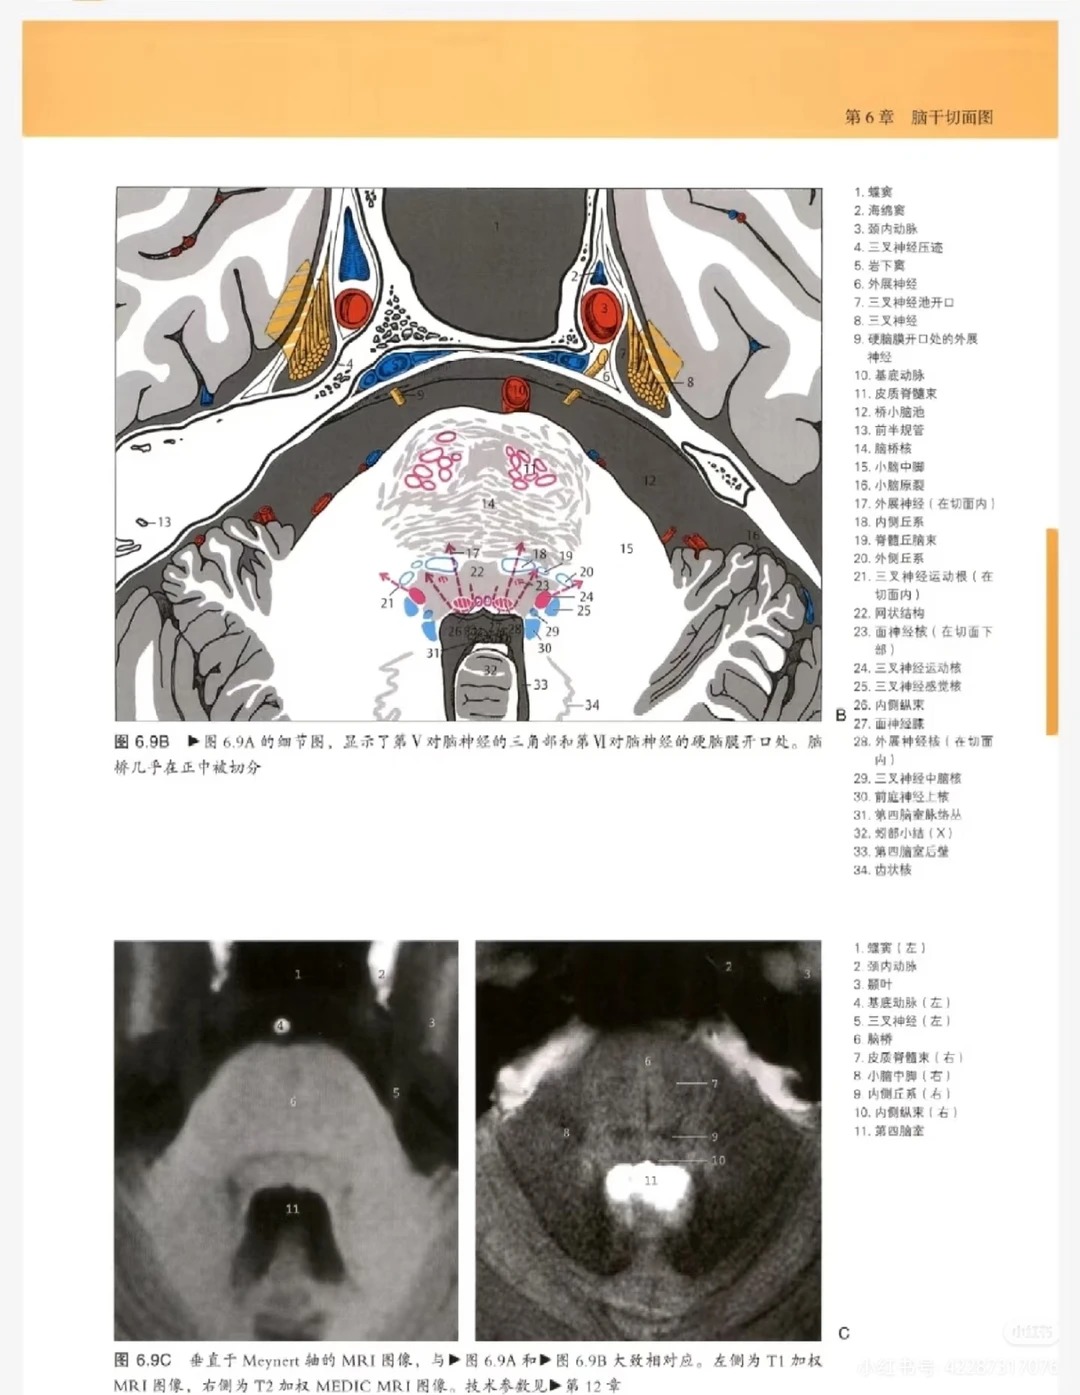

2. 影像与解剖深度结合,破解看片难题:这是本书的核心王炸卖点,每一张颅脑影像图旁边,均配套高清解剖图+手绘示意图,精准对应解剖结构与影像表现,清晰标注关键部位,让使用者能快速将影像表现与解剖结构关联起来,彻底解决“对着片子找不着北、看不懂脑回路”的核心痛点,提升看片与诊断能力。

4. 高清大图,标注精准,直观易懂:全书采用高清大图呈现,影像图、解剖图清晰可辨,标注精准细致,关键解剖结构、病变部位一目了然,对于影像这种“看图说话”的学科,能大幅提升看片与学习效率,无论是临床看片还是日常学习,都能快速抓取核心信息。

• 影像+解剖对照篇:每一张影像图配套高清解剖图+手绘示意图,精准对应解剖结构,标注关键部位,帮助使用者快速关联影像与解剖,看懂颅脑结构。